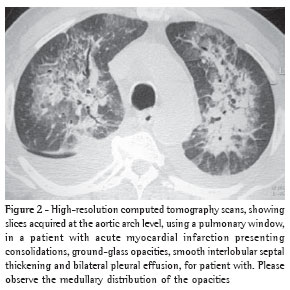

Overall, ground-glass opacities and thickening of the interlobular septa were the most common findings, occurring in 100% of the cases (Figures 1 and 2).

The thickening of the interlobular septa was bilateral in thirteen cases (Figures 1-4) and unilateral in two, also in the patients with fibrosing mediastinitis. In all cases, the thickening was of the smooth type.

Consolidation was detected in only five (33%) of the patients (Figures 2 and 5). All of the patients presented bilateral consolidations, In two cases, the distribution was asymmetric, with a 'bat-wing' aspect, and predominant in the upper right lobe (cases of mitral valve chordae rupture) (Figure 5).

Pleural effusion was the third most common tomographic finding overall and was the most common nonparenchymal finding, being found in 13 patients (87%), predominantly in the bilateral form (n = 11) (Figures 1-3).